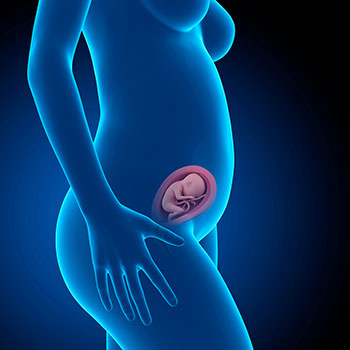

Na 22ª semana de gravidez, o teu útero pode já ter superado o umbigo. Na carinha do bebé já se distinguem claramente as pálpebras, sobrancelhas e pestanas. A partir de agora, o seu cérebro vai aumentar cerca de 90 gramas por mês.

Chegado às 22 semanas de gravidez, o bebé mede cerca de 27,8 centímetros do cocuruto até às nádegas e o seu peso médio é de 430 gramas.

Grávida de 22 semanas

Agora, todos os seus ossos contêm medula óssea que pode produzir glóbulos, e a sua pele armazena no seu interior finas capas de gordura corporal que são essenciais para o completo desenvolvimento do sistema nervoso. À medida que o bebé vai armazenando gordura sob a pele, esta vai tornando-se translúcida e as suas veias tornam-se menos visíveis.

Idade do feto: 20 semanas.

Chegada à 22ª semana de gravidez, é normal que já tenhas engordado entre 5 e 6 kilos e que a tua cintura já tenha desaparecido.

As barrigas têm diferentes tamanhos e formas, mesmo estando na mesma semana de gestação.

Este medida deveria fazer correspondência com a semana de gestação, embora haja uma baliza de dois centímetros acima e abaixo da margem. Tal significa, por exemplo, que na 22ª semana de gravidez uma barriga saudável deverá medir entre 20 e 24 centímetros.